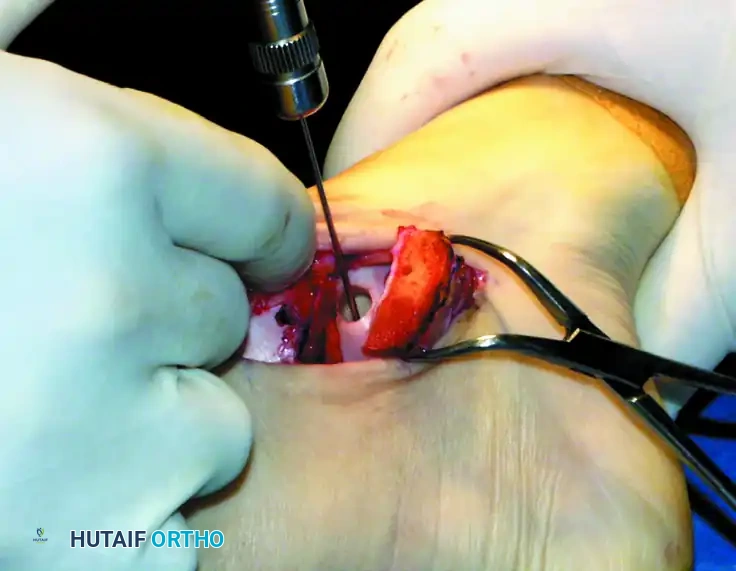

Step 3: Graft Insertion and Seating

Bring the donor harvester containing the graft to the ankle. Align the harvester perfectly with the recipient socket.

Insert the cylindrical graft carefully into the recipient hole using the specially designed extruder or collared pin through the back of the donor harvester.

CRITICAL PITFALL: Do not remove the OATS harvester from the recipient site before the completion of full graft extrusion. Furthermore, do not allow the harvester to deviate from the insertion angle during extrusion. Either of these technical errors will place sheer stress on the graft and cause a catastrophic fracture of the donor core.

Once the graft is extruded into the socket, use the oversized sizer-tamp to gently tap the core until it is perfectly flush with the surrounding native cartilage. A proud graft will cause "kissing lesions" on the tibial plafond, while a sunken graft will fail to bear load, leading to fibrocartilage infill and cyst formation.

Test the range of motion of the ankle under direct visualization to ensure that the graft is well seated, secure, and does not impinge during articulation.